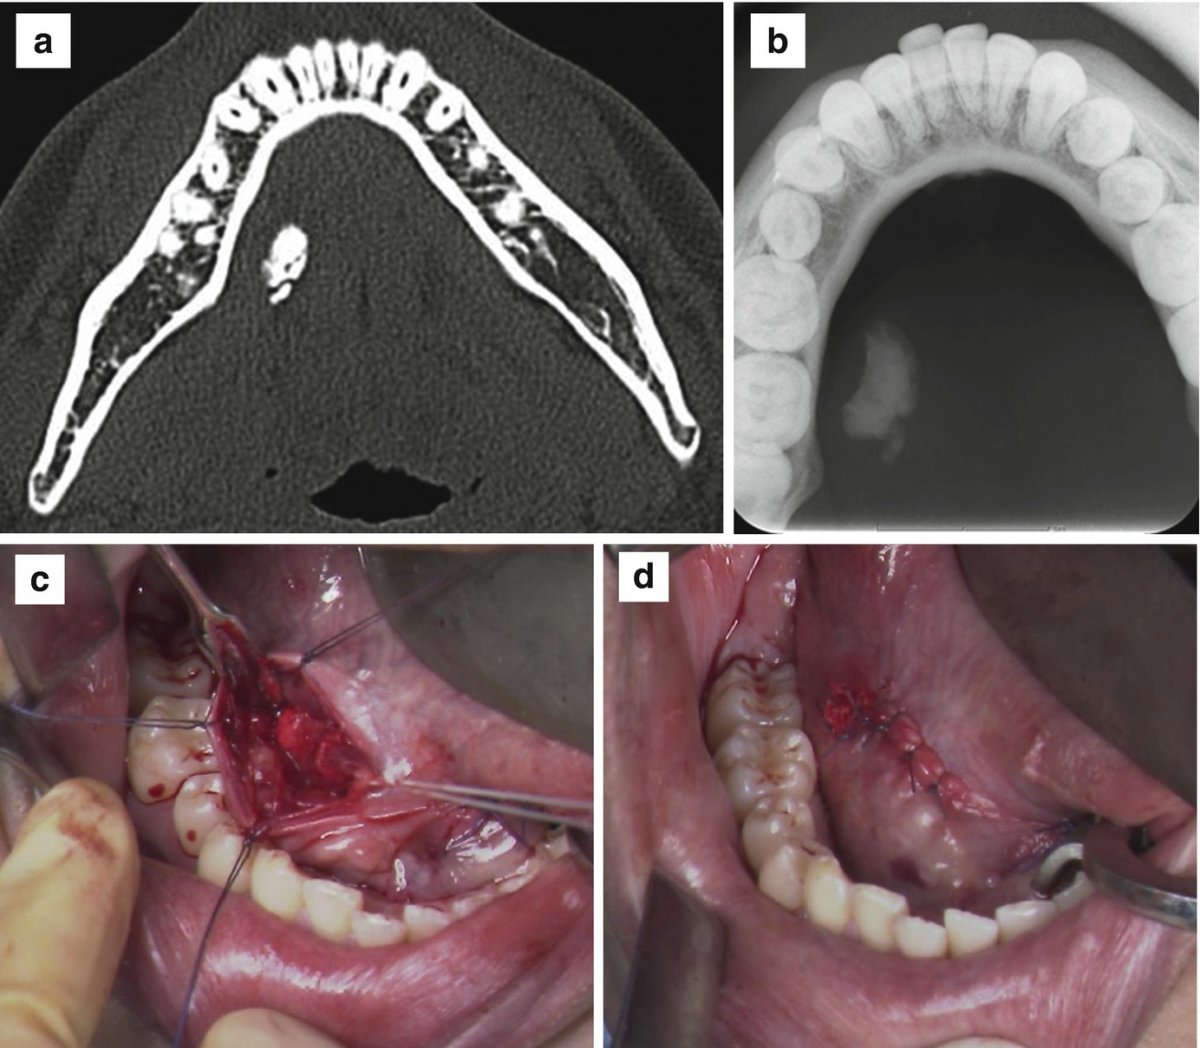

I did some plain research on teeth about the structure and some unusual silhouette deture.